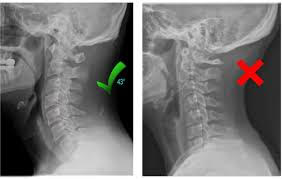

Using advanced X-ray analysis, we deliver specific spinal adjustments that restore alignment throughout the entire spine—removing interference to the nervous system and optimizing neurological function. This allows your body to heal and perform at its highest potential, naturally.

Our Specific Chiropractic adjustments are precise, gentle techniques designed to correct spinal misalignments (subluxations) that interfere with proper nervous system function.